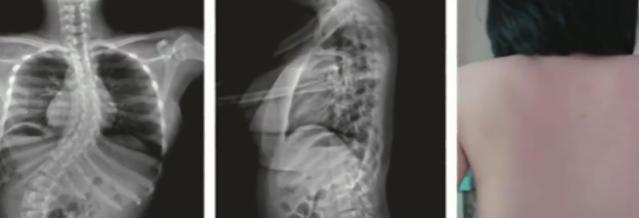

“瘫痪之后,孩子只能依靠轮椅生活,久而久之,脊柱也会出现弯曲。”朱泽章表示,不仅双手生活能力受限,心肺等多个脏器功能也因脊柱变形受到压迫。无奈之下,父母将她送到南京某医院脊柱外科就诊,进行微创矫形治疗。